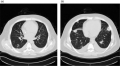

Isolated pulmonary valve endocarditis masquerading as community-acquired pneumonia Journal of Community Hospital Internal Medicine Perspectives